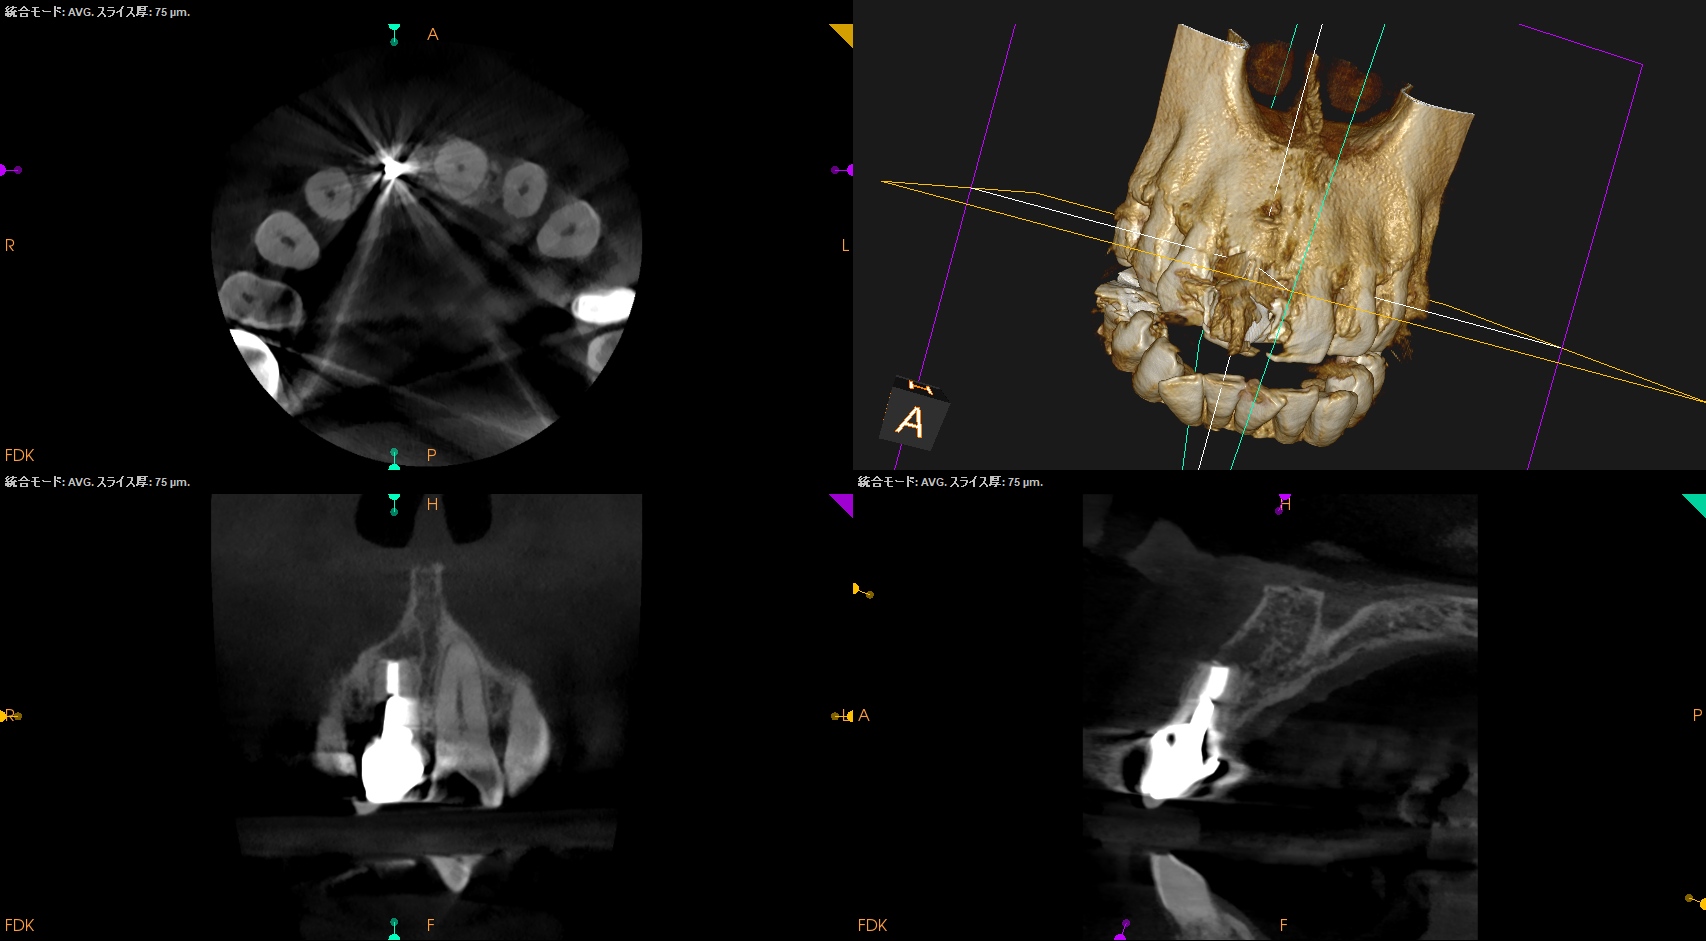

左右の同名歯を比較した。

#8は#9に対して2mm短かかった。

これは外部吸収で消失したのかもしれない。

いずれにしても、#8はこの部分から3mm削るとメタルポストコアにRetroprepが及びそうである。

したがって、1mmだけ切断してRetroprepすることにした。